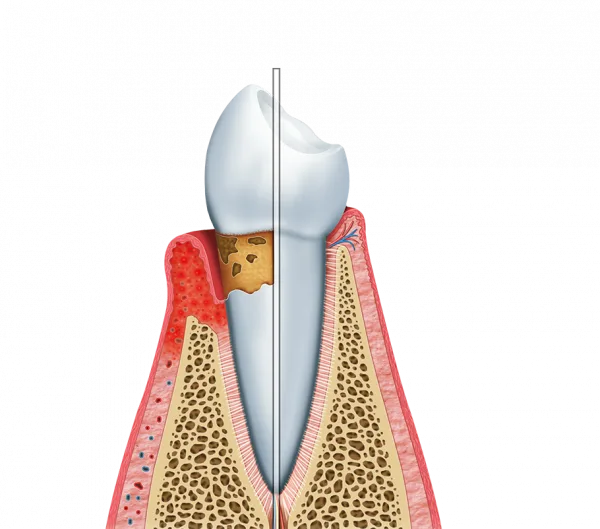

A periodontite tratamento é crucial para manter a saúde bucal.

Essa condição é uma infecção grave que afeta as gengivas e os tecidos de suporte dos dentes.

Se não tratada, pode levar à perda dos dentes e a complicações mais sérias.

Causas da periodontite

- Acúmulo de placa bacteriana

- Falta de higiene bucal adequada

- Fatores genéticos e hormonais

Um tratamento eficaz remove a placa e o tártaro acumulados.

Isso ajuda a restaurar a saúde das gengivas.

Além disso, promove a preservação dos dentes naturais.

Tratamentos não cirúrgicos

Os tratamentos não cirúrgicos incluem a raspagem e alisamento radicular.

Esses procedimentos ajudam a remover a placa e o tártaro.

Eles são menos invasivos e geralmente têm um tempo de recuperação mais curto.